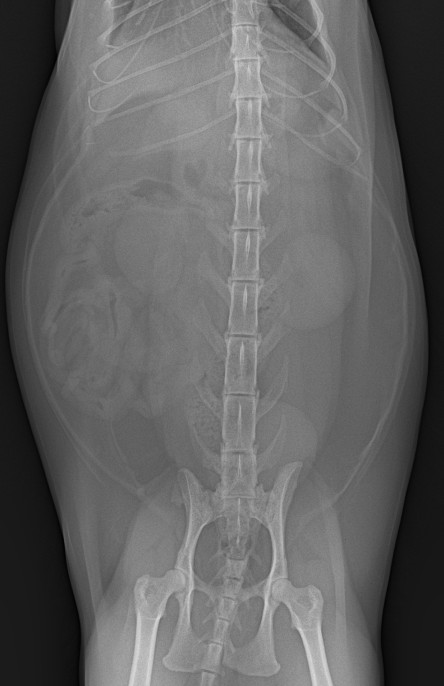

혈액검사에서는 주요 장기 수치, 염증 수치, 전해질 균형 등을 확인했고, X-ray는 흉부·복부 전반의 장기 구조를 점검했습니다. 초음파는 장기 실질 구조나 미세한 이상까지 확인할 수 있어 검진의 핵심 항목으로 포함됩니다. 치과검사는 일반적으로 마취가 동반되어, 구강전용 엑스레이 촬영을 해야 정확한 판단이 가능하지만 치과전문 병원인 만큼 육안으로 기본적인 검사는 해드리고 있습니다.